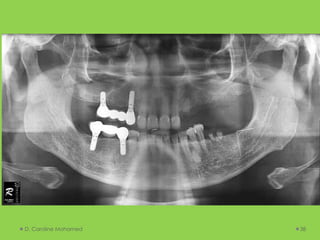

D. Caroline Mohamed 38